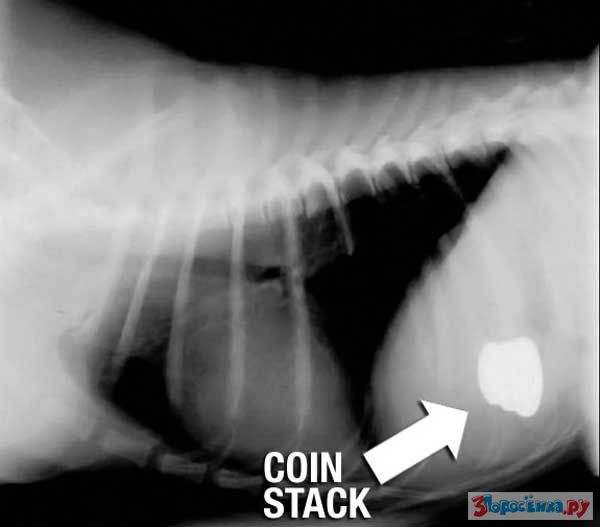

Нет ничего не перевариваемого

Некоторые собаки видимо полагают что их желудок способен переварить все на свете.